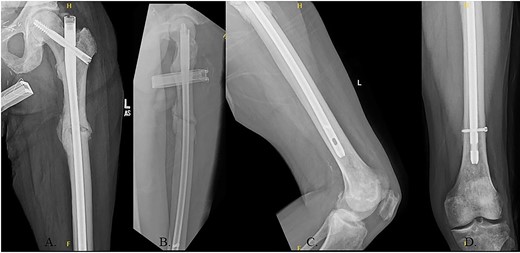

The hip was extended, and a ball-tipped guidewire was successfully passed across the fracture site to a center–center positionwithin the canal at the level of the knee (Fig. 4C and D). Sequential 0.5-mm reaming from 9 to 13 mm prepared for an 11 × 400 mm, 125° Gamma3® intertrochanteric rod (Stryker© Kalamazoo, MI), with a 95-mm cephalomedullary screw and ×2 distal lateral to medial interlocking 5.0-mm screws (Fig. 5A–D). Through the course of the procedure, 400 cc of blood loss necessitated two units of packed red blood cells.

The patient immediately was weight-bearing as tolerated to the operative extremity and worked with physical therapy (PT) to include 80 ft on post-operative day (POD) #2 with use of a front-wheeled walker. He continued to progress with PT and was discharged home POD #8 with home health/PT. At 12 months, the patient denied pain, and XRs demonstrated robust callus formation and bridging healing at the fracture site (Fig. 6).

(A) 12-month post-operative AP radiograph of left hip; (B) 12-month post-operative lateral radiograph of left hip; (C) 12-month post-operative lateral femur radiograph; (D) 12-month post-operative AP distal femur radiograph.